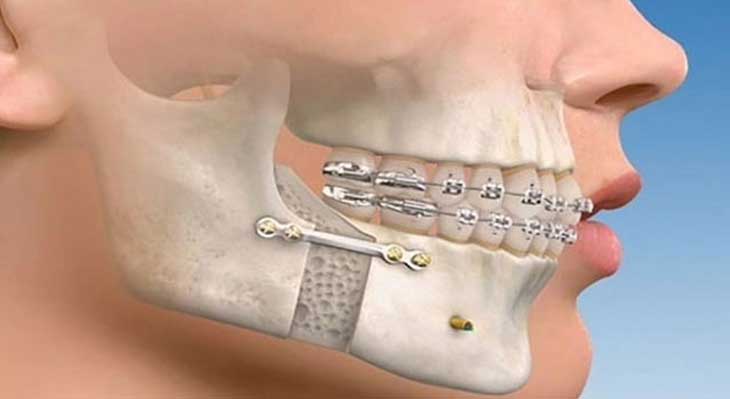

علاوه بر براکت ها و سیم های اصلی، گاهی برای دستیابی به نتایج پیچیده تر و بهینه سازی درمان، از ابزارها و تکنیک های کمکی استفاده می شود. این ابزارها به متخصص ارتودنسی اجازه می دهند تا نیروهای دقیق تری را در جهات خاص اعمال کند.

- کش های ارتودنسی (الاستیک ها): این کش کوچک که بین قلاب روی براکت فک بالا و پایین قرار می گیرد، برای اصلاح رابطه بایت و هماهنگ کردن دو فک با یکدیگر ضروری است.

- مینی اسکرو ها (TADs): این پیچ های کوچک تیتانیومی که به طور موقت در استخوان فک قرار داده می شوند، به عنوان لنگرگاه های قدرتمند برای اعمال نیروهای پیچیده و کنترل شده عمل می کنند.